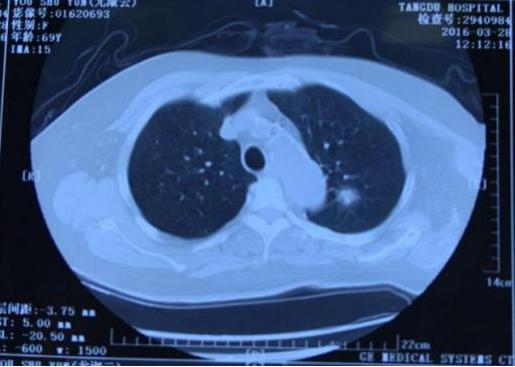

肺部结节是指≤3cm的肺部圆形病变,无卫星灶、无淋巴结及远处播散。肺部小结节是指≤1cm的结节,又称亚厘米结节。还有一个经常在肺部CT检查影像报告上看到的术语GGO,它是指肺部磨玻璃结节,是一种特殊类型的肺部结节,表现为密度轻度增高的云露状淡薄影/圆形结节,样子像磨砂玻璃一样,所以叫磨玻璃影。研究表明,18%-63%的毛玻璃样小结节是早期肺癌;肺部结节可以是弥漫性散生长,也可以仅聚集在局部。一般而言,弥漫性生长的结节良性病变的可能性大,局灶性生长的容易是肺部肿瘤。

西安交通大学附属胸科医院(西安市胸科医院)呼吸与危重症医学科设立 “肺结节一站式“综合门诊,构建并优化了肺结节/肺癌精准诊治体系,为就诊患者提供“一站式”服务:网上预约挂号-影像学检查-三维重建数字肺分析-必要时气管镜/内科胸腔镜检查-制定治疗建议-随访;同时,对于疑难肺结节患者,将由呼吸与危重症医学科、胸外科、肿瘤科等多学科专家共同商讨和制定个性化治疗方案,提高肺结节诊断的准确率,真正实现“病人不乱跑、医生围着病人转”的一站式服务。

病例1: 巩先生,体检发现左肺毛玻璃小结节,用EBUS-GS超声支气管镜进行检查,病理结果:隐球菌感染。